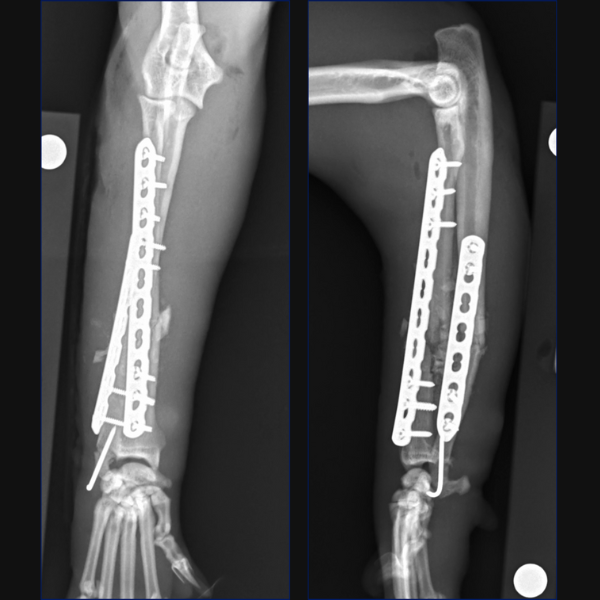

For this case, as anatomic reduction was possible, an open approach was elected with stabilization of the radius being achieved through a craniolateral approach and use of a 1.5/2.0 notched T-plate. 3 locking screws were placed distal to the fracture site with 2 locking and 2 non-locking screws being used proximally. Compression was attempted, but you can see that a small gap remains on the transcortex, so I could have pre-stressed my plate a little better.

Reduction of the radial fracture completely reduced the ulnocarpal luxation. We assessed for instability intraoperatively using the same technique which is reported in people which involves stabilizing the radiocarpal joint with one hand and then trying to move the ulna independently in a dorsal and palmar direction. Based on our assessment, no instability was palpable and as such, no distal radioulnar fixation was considered necessary.